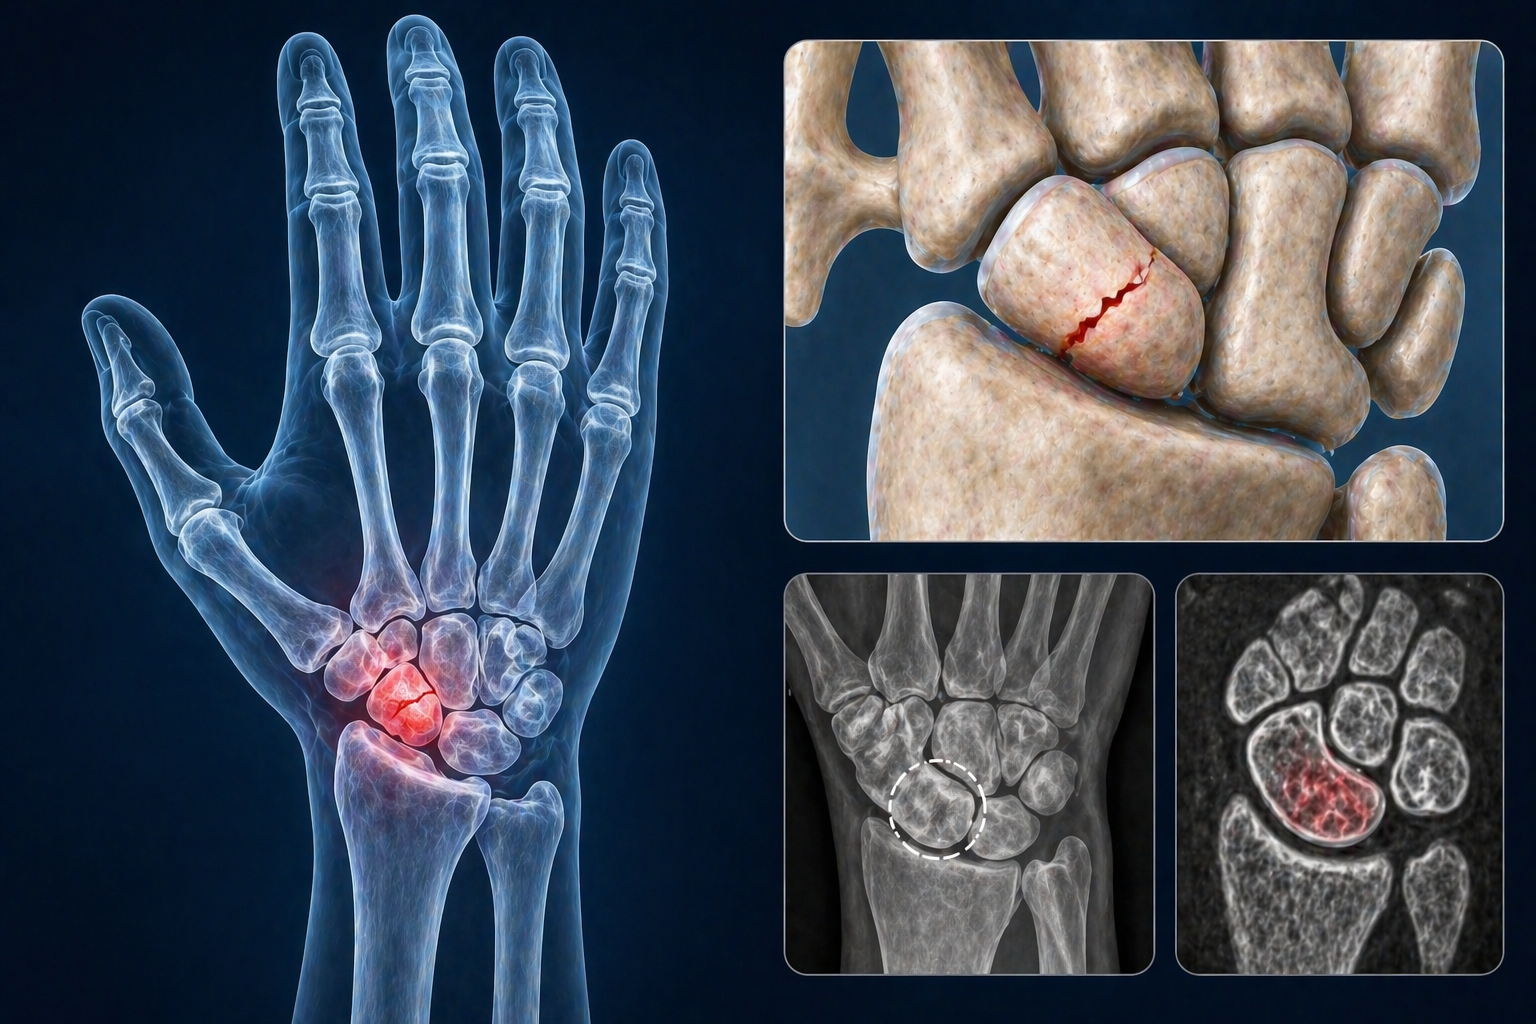

Из всех переломов костей запястья переломы ладьевидной кости встречаются чаще всего и составляют 60−70% от общего числа переломов данной локализации.

Часто под жалобами на «растяжение запястья» может скрываться перелом ладьевидной кости. Эту травму часто удаётся исключить в острой стадии, опираясь на данные объективного осмотра. Обычные рентгенограммы не позволяют исключить этот перелом.

Даже несмотря на это дополнительно обследование, перелом может не определяться на протяжении 6 недель после травмы. В острой стадии не рентгеновских снимках не удаётся увидеть до 30% переломов ладьевидной кости. Косвенным признаком острого перелома ладьевидной кости является смещение её жировой полоски. Однако, по данным одного исследования, этот признак наблюдался лишь в 50% случаях рентгенологически скрытых переломов ладьевидной кости. В некоторых случаях помогает сравнительный снимок неповреждённого запястья.